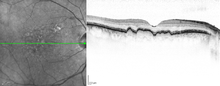

Macular soft drusen in the right eye of a 70-year-old male. | |

Drusen (singular, "druse") are tiny yellow or white accumulations of extracellular material that build up between Bruch's membrane and the retinal pigment epithelium of the eye. The presence of a few small ("hard") drusen is normal with advancing age, and most people over 40 have some hard drusen. However, the presence of larger and more numerous drusen in the macula is a common early sign of age-related macular degeneration (AMD).

Drusen are associated with aging and macular degeneration are distinct from another clinical entity, optic disc drusen, which is present on the optic nerve head.[1] Both age-related drusen and optic disc drusen can be observed by ophthalmoscopy. Optical coherence tomography scans of the orbits or head, calcification at the head of the optic nerve without change in size of globe strongly suggests drusen in a middle-age or elderly patient.